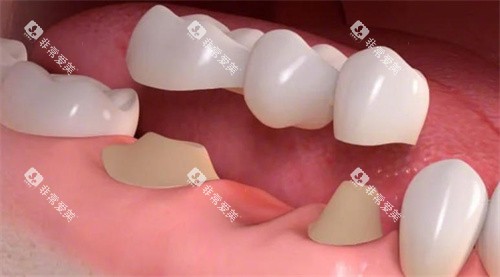

固定假牙(如烤瓷桥)在牙槽骨萎缩导致基牙条件变化时,需要重新评估基牙的支持能力。可能需要增加基牙数量或采用桩核冠修复等辅助固位方式,以确保修复体的牢固性。

种植牙的适用范围广泛:单颗牙缺失时,无需磨损邻牙,直接在缺牙位置植入即可;多颗牙连续缺失时,可通过植入少量种植体作为“桥墩”,搭配桥体修复;全口牙缺失时,甚至可以通过4-6颗种植体固定全口牙冠,避免传统全口假牙容易脱落的问题。